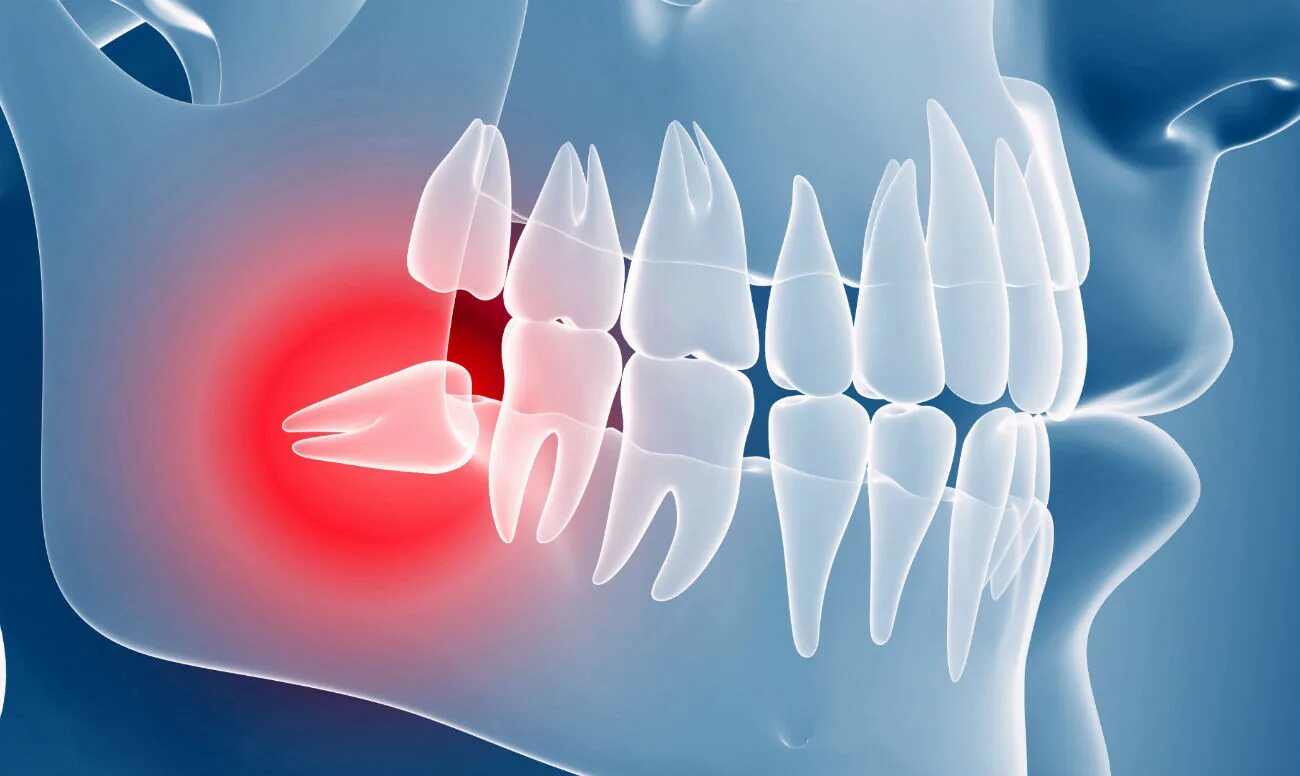

Зуб дистопирован